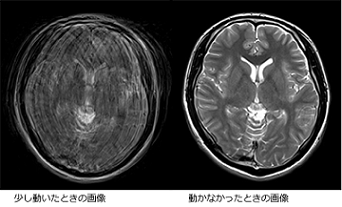

⑥撮像は何回か繰り返して行います。撮影している間に動いてしまうと画像がぶれてしまうため、じっとしていてください。

そのため転びやすくなったり、一人で座らせていても横や後ろに倒れやすくなりますので転倒・打撲などに注意してください。 - 検査中に動いてしまうと

動く程度によっても異なりますが、画像が作成できなかったり、画像になっても診断上、支障をきたす場合がほとんどです。